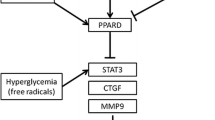

Many cytokines including CTGF and RAGE contribute to myocardial fibrosis in various animal models, and although many researchers have tried to find a way to reduce myocardial fibrosis by direct antagonism and inhibition of cytokines [5, 11, 19, 25], findings could not be translated into clinical applications and did not provide further insight into the mechanisms for myocardial fibrosis suppression. Peroxisome proliferator-activated receptor (PPAR)-γ agonists inhibit CTGF expression in cardiac fibroblast [17] and attenuate angiotensin II-induced cardiac fibrosis by inhibiting myocardial macrophage infiltration [5]. PPAR-γ agonists have also been shown to inhibit RAGE expression in vascular endothelial cells and vascular smooth muscle cells [18]. Moreover, PPAR-γ agonists have been tested as potential therapeutic agents in the suppression of collagen synthesis in the lung and liver, both in vitro and in vivo [12, 20]. However, the effects of PPAR-γ agonists on myocardial CTGF and RAGE expression have not been defined, and few studies have investigated whether PPAR-γ activation can attenuate cardiac fibrosis in overt diabetes in vivo. We posited that PPAR-γ agonists may inhibit the expression of RAGE and CTGF in association with attenuation of myocardial fibrosis in the diabetic heart, and utilized serial echocardiography to examine LV diastolic function alterations induced by rosiglitazone, as a pure PPAR-γ agonist, while analyzing myocardial RAGE and CTGF expression to address the effects of PPAR-γ activation in the hearts of T2D rats.

Our study revealed that PPAR-γ activation in diabetic rats could suppress both myocardial RAGE and CTGF expression and fibrosis. In untreated OLETF rats, RAGE and CTGF proteins were expressed at significantly higher levels in the myocardial interstitium and endothelial cells. Rosiglitazone treatment significantly suppressed myocardial expression of RAGE and CTGF. RAGE stimulates the release of profibrotic growth factors including CTGF in the diabetic environment [26]. Recently, PPAR-γ agonists have been reported to down-regulate basal as well as TNF-α-induced RAGE expression in endothelial cells and mesangial cells and to subsequently inhibit AGE-induced MCP-1 expression [18, 19]. Since RAGE is upregulated by NF-κB activation [27] and PPAR-γ agonists reduce RAGE expression by inhibiting NF-κB expression in endothelial and mesangial cells, we speculated that rosiglitazone might suppress RAGE expression by inhibiting NF-κB activation in the myocardium, resulting in reduced CTGF expression [18, 19]. Although PPAR-γ agonists have been reported to inhibit RAGE and CTGF expression in vitro and in the glomeruli of rat kidneys, and to suppress CTGF in cardiac fibroblasts, no prior studies have defined the effect of PPAR-γ agonists on RAGE and CTGF expression in the myocardium of overt diabetic animals. Several studies have shown an association between PPAR-γ agonist treatment and extent of myocardial fibrosis. Yao et al. [33] was the first to report that a PPAR-γ agonist could reduce myocardial fibrosis in diabetic rats. In their T2D rat model study, however, the PPAR-γ agonist was administered from the age of 5 weeks, prior to the development of overt diabetes. This experimental design might confuse interpretations of the effects of the PPAR-γ agonist on the antifibrotic mechanisms in the diabetic heart because the PPAR-γ agonist has been reported to effectively prevent or delay diabetes development in diabetic rats [15]. In contrast with Yao’s report, we used a rat model with overt diabetes. Recently, Caglayan et al. [5] reported that PPAR-γ ligands attenuate angiotensin II-induced cardiac fibrosis by inhibiting myocardial macrophage infiltration. Our study further confirmed PPAR-γ agonist-mediated suppression of cardiac fibrosis, especially in diabetes-related fibrosis in vivo and also showed that PPAR-γ agonist treatment can lower myocardial expression of RAGE and CTGF, which may be involved in the process of diabetes-related cardiac fibrosis.

This study has several limitations. First, the reduction of myocardial fibrosis and RAGE expression in rosiglitazone-treated diabetic rats may result from better glycemic control with associated decreased AGE production. However, since RAGE has been reported to act independently of AGEs in cardiac remodeling [6, 24], RAGE expression status seems to be more relevant to myocardial fibrosis. Studies using heart-specific PPAR-γ knockout mice are needed to address whether the improvements in diastolic dysfunction are mediated through a direct action of rosiglitazone on the myocardial tissue or through its improvement of the metabolic milieu. Second, we did not investigate the causality between CTGF and RAGE expression reduction and decreased cardiac fibrosis after rosiglitazone treatment. Marx et al. [18] reported that the strong anti-inflammatory effect of rosiglitazone is achieved by inhibiting NF-κB activation and consequent suppression of TNF-α-induced endothelial expression of RAGE. Further studies are required to elucidate such causality.